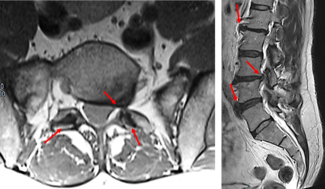

Le vertebre presentano posteriormente un anello (fatto di “peduncoli” e “lamine”) che formano, impilati fra loro come sono, un vero e proprio canale. Da oltre 90 anni è noto che il disco intervertebrale, una specie di cuscinetto ammortizzatore fra una vertebra e l’altra, a livello lombare (più che in altre sedi) può “sfiancarsi” posteriormente e andare a comprimere le più varie terminazioni nervose dolorifiche all’interno dell’angusto canale vertebrale.

Il canale ha una sezione di pochi centimetri quadrati e ospita nervi, legamenti, arterie, vene, grasso il sacco durale (o dura meninge) che avvolge le lunghe radici nervose che - uscendo dal canale vertebrale - si dirigono alla zona lombare, glutea e agli arti inferiori. Nel sacco è poi raccolto il liquido cerebrospinale (o liquido cefalorachidiano, o “liquor”): nel canale c’è una gran folla, come si vede.

Il "canale ristretto"

La compressione può avvenire anche da parte di deformità artrosiche che si formano nelle articolazioni (le “faccette”) che connettono posteriormente le vertebre fra di loro (immaginiamo le conseguenze di deformazioni delle nocche in una mano artrosica ma all’interno del canale vertebrale, rigido e poco spazioso).

Si parla allora di “canale ristretto” o “stenosi lombare”: una sindrome nella quale al dolore si associa una ridotta distanza di marcia. Dopo 50-300 metri “le gambe non vanno più”.

Ci siamo dimenticati che il canale vertebrale è foderato da un fitto reticolo venoso scoperto soltanto nel 1940. Anche lui può venire facilmente compresso e quindi dilatarsi, oppure si può dilatare se il flusso venoso non viene “smaltito” facilmente (come nel riposo, quando manca “pompa” muscolare, o in caso di insufficienza cardiaca o respiratoria). E se le vene diventano varicose creano anch’esse compressione. Inoltre il sangue al loro interno tende a ristagnare e una dolorosa flebite è in agguato. In breve, al dolore può contribuire la insufficienza venosa locale.